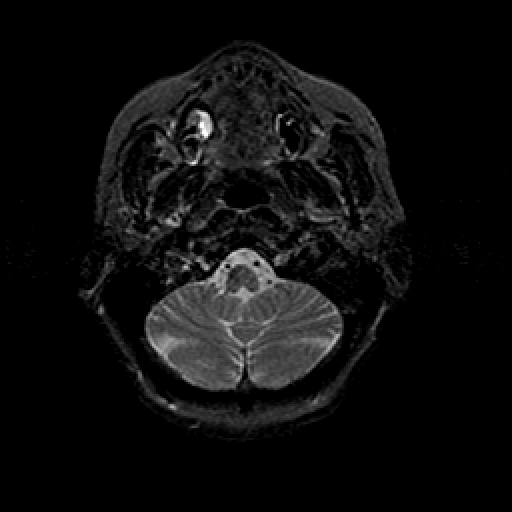

T2-weighted structural MR: Slice 8

Slice 8